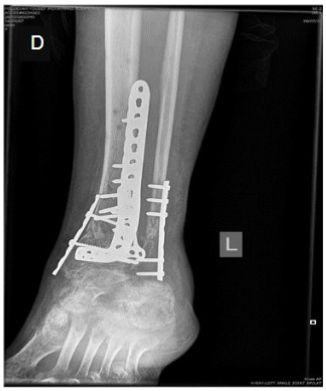

Once the 3D model was generated, it was used to simulate the surgical approach and plan the precise placement of internal fixation devices, including screws and plates. The ability to visualize the fracture in three dimensions significantly enhanced the surgical team’s ability to avoid potential complications, such as screw loosening, misalignment, or malposition of the bone post-fixation. These complications, common in traditional methods, are mitigated by the enhanced precision of 3D modeling, which allows the surgeon to plan for optimal screw positioning and alignment prior to the procedure.

- Enhanced Precision: The ability to visualize complex fracture patterns in 3D allowed the surgical team to place fixation devices with higher accuracy. This precision reduces the likelihood of postoperative complications, such as malalignment or loosening of the hardware, which are common challenges in Pilon fracture repair.

- Reduced Risk of Postoperative Issues: The ability to plan and rehearse the surgical approach virtually significantly reduces the risk of intraoperative surprises, ultimately resulting in better alignment and fewer postoperative complications. In this case, the operative time was reduced by 50%, as the surgeons were able to proceed with a clear, practiced plan. This reduction in surgical duration is particularly important as it decreases anesthesia time, which in turn may lower the risk of anesthesia-related complications and improves recovery outcomes.